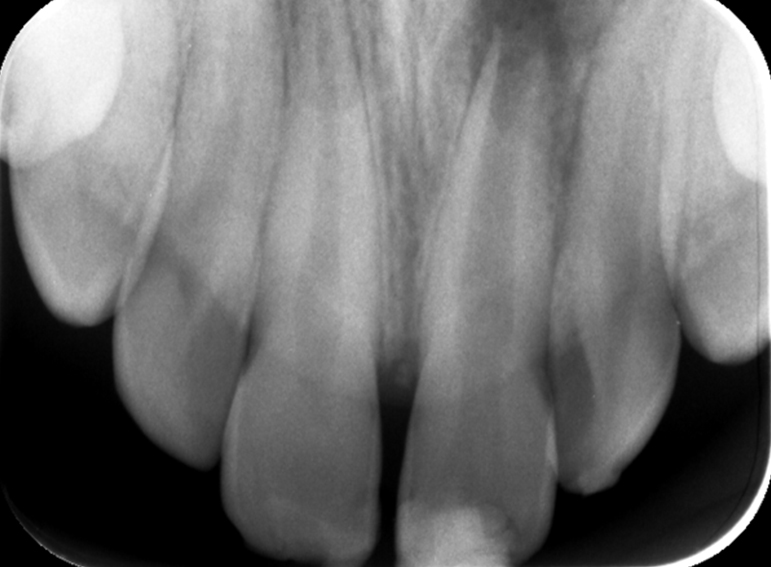

Root canal treatment including apexification of an immature incisor following dental trauma.